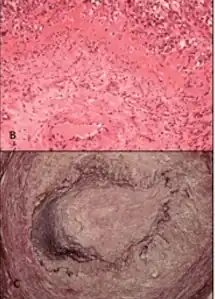

| b,c) Giant-cell arteritis | |

Giant cell (temporal) arteritis. Chronic vasculitis of both large and medium vessels, primarily affecting cranial branches of the arteries arising from the aortic arch. At least three out of five criteria yields sensitivity and specificity of 95 and 91%:

- Temporal artery biopsy showing vasculitis with mononuclear cell infiltrate or granulomatous inflammation, usually with multinucleated giant cells